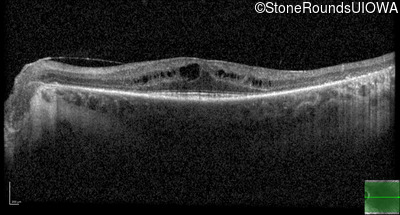

Optical Coherence Tomography - Right - 20/20 -2

Exemplar / OCT Stack

OCT Stack